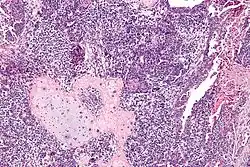

Le carcinosarcome est une tumeur maligne associant des aspects carcinomateux et sarcomateux[1]. Il est fréquemment de localisation utérine.